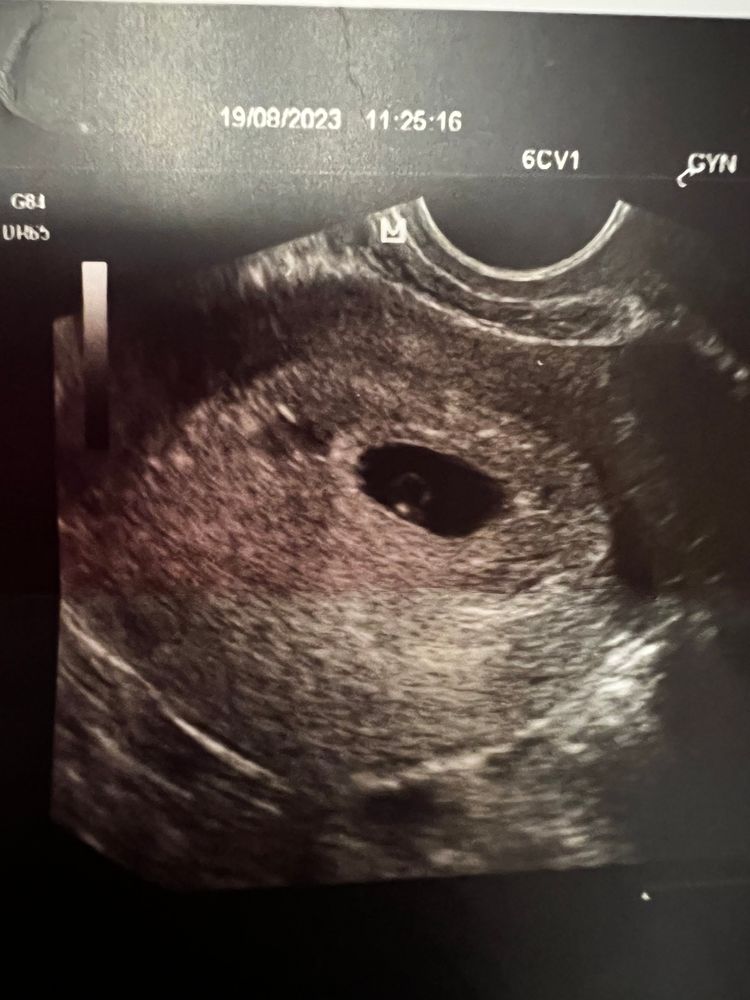

на просторах интернета , искала информацию , о выражении « кольцо с бриллиантом» после сегодняшнего узи 😁 нашла этот сайт

А точнее…второй!